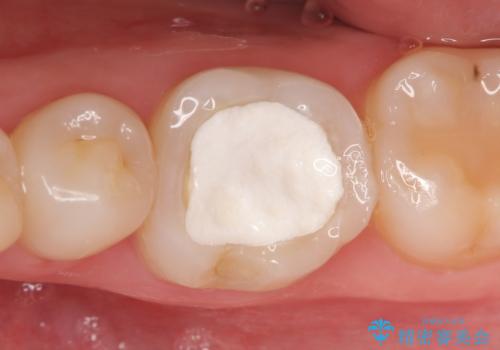

- 他院にて左下6番目の歯の根管治療を行っていたが、痛みが引かず抜歯を提案されたため、何とか歯を残せないかと当院にいらっしゃった方の症例です。

顕微鏡下で精密根管治療を行い、症状の緩解を確認後、オールセラミッククラウンによる補綴を行いました。